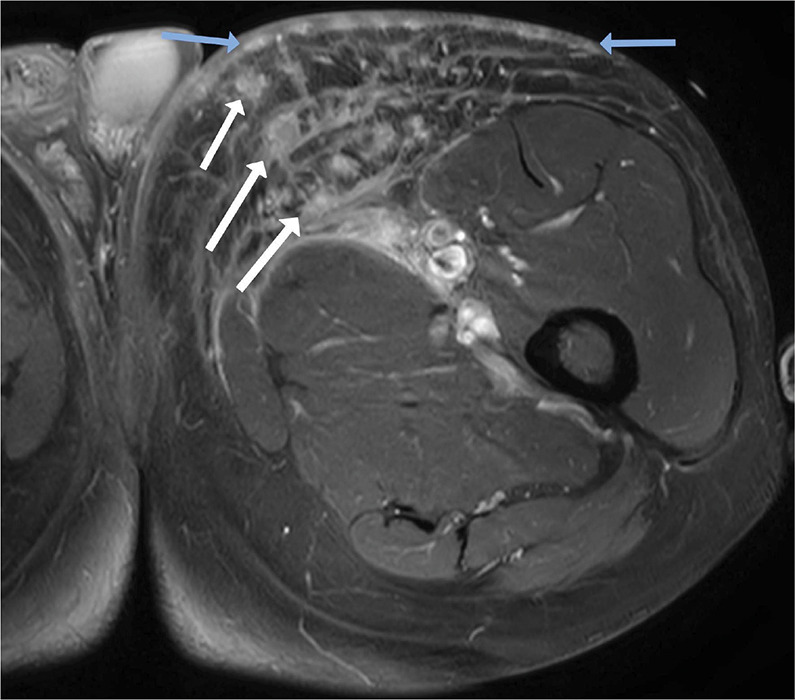

教学点:卡波西肉瘤是一种罕见的疾病,最常见于人类免疫缺陷病毒(HIV)患者、接受免疫抑制剂的患者或非洲患者。放射成像在促进诊断和随访方面发挥作用,目前主要是正电子发射断层扫描-计算机断层扫描(PET - CT)(1)。

Teaching point: Kaposi sarcoma is a rare disease most commonly occurring in patients with human immunodeficiency virus (HIV), in patients receiving immunosuppressants or in African patients. Radiological imaging has a role in facilitating the diagnosis and follow‑up, currently primarily with positron emission tomography-computed tomography (PET‑CT) (1).